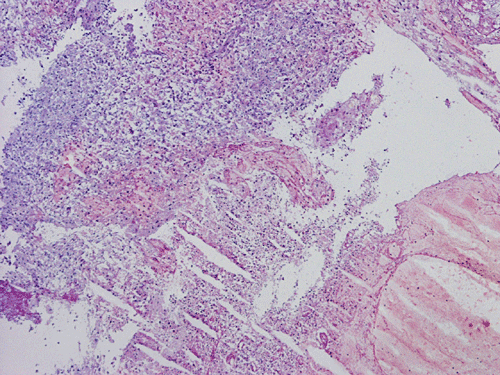

He was admitted again. In this admission, he developed left intraparenchymal hemorrhage associated with the enhancing mass, edema, and 0.4 cm left to right midline shift. A craniectomy was performed to evacuate the blood and biopsy the enhancing mass. The followings are representative images from the biopsy material.

![]() |

|

A. Squash |

B. Squash |

C. Squash |

D. Squash |

E. Squash |

F. Frozen |

G. Frozen |

Panel A to E are intra-operative cytologic preparation, Panel E to J are frozen section, Panel K to N are permanent sections.